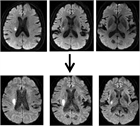

1. 片麻痺を数分以上生じた一過性脳虚血発作の患者には、すみやかに脳MRI検査(拡散強調画像)を施行することが勧められる(推奨度1)。脳MRI検査をすみやかに実施できない場合でも、少なくとも脳CT検査を試行して脳出血を除外したうえで抗血栓治療を開始し、可及的早期に脳MRI検査を実施する(推奨度1)